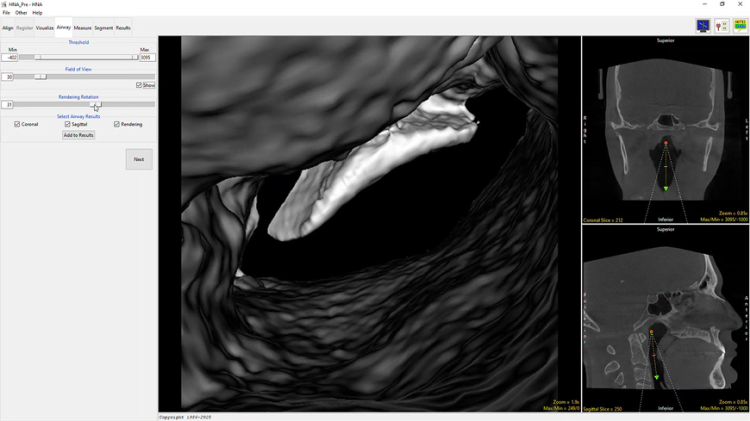

Airway

The Airway tab in the HNA app is designed to provide an internal rendering or endoscopic view of the airway.